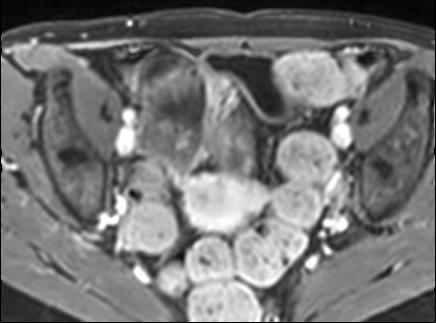

Bệnh nhân nữ 48 tuổi, đang điều trị bằng thuốc kháng TNF, được chỉ định nội soi đại tràng.

Phát hiện hẹp lòng ruột ở đại tràng sigma, không thể vượt qua được khi nội soi.

MR-enterography được thực hiện để đánh giá mức độ lan rộng của chỗ hẹp.

Ruột non bình thường, nhưng ghi nhận các đoạn hẹp ở đại tràng xuống và đại tràng ngang.

Cả hai đoạn hẹp đều có thành ruột dày đến 8 mm và ngấm thuốc rõ rệt theo kiểu niêm mạc ở đại tràng xuống và kiểu phân lớp ở đại tràng ngang.

Giãn ruột trước chỗ hẹp được ghi nhận ở cả hai đoạn.

Do các chỗ hẹp này không hiện diện khi nội soi đại tràng trước khi điều trị kháng TNF, nhiều khả năng chúng đã hình thành trong quá trình điều trị.

Do đó, quyết định phẫu thuật cắt đại tràng gần toàn bộ với miệng nối hồi-sigma đã được đưa ra.